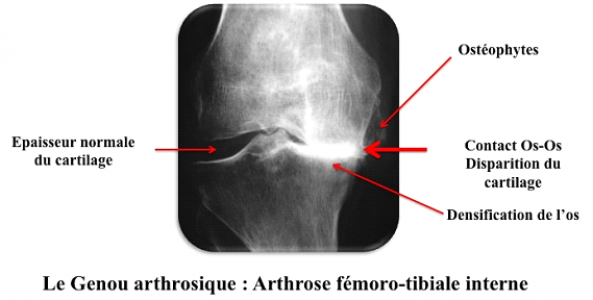

Lorsqu’il existe une arthrose vraie on observe sur la radiographie une disparation de l’interligne articulaire et un contact entre le fémur et le tibia ou la rotule et le fémur. D’autres signes indirects d’arthrose peuvent être présents, densification de l’os sous chondral, présence d’ostéophytes (bec de perroquet) parfois corps étrangers libres dans l’articulation, petite géode à l’intérieur de l’os.

Genou arthrosique : arthrose fémoro-tibiale interne